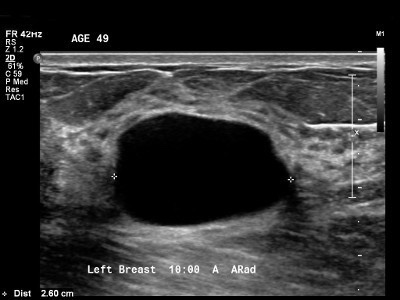

Ultrasound imaging of the breast produces a picture of the internal structures of the breast.

The primary use of breast ultrasound is to help diagnose breast abnormalities detected by a physician during a physical exam (such as a lump) and to characterize potential abnormalities seen on mammography or breast magnetic resonance imaging (MRI).

Ultrasound imaging can help to determine if an abnormality is solid (which may be a non-cancerous lump of tissue or a cancerous tumor), fluid-filled (such as a benign cyst) or both cystic and solid.